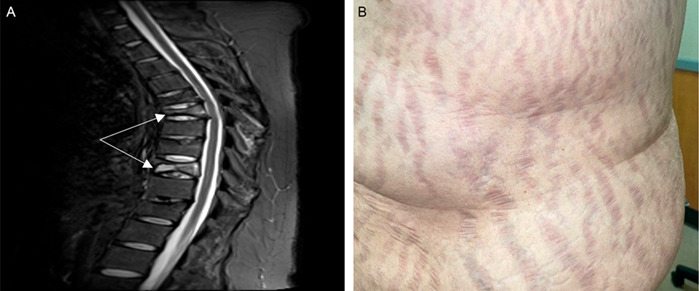

Clinical Images: Vertebral compression fractures and striae in Cushing's disease.

临床表现:库欣病的椎体压缩性骨折和条纹。